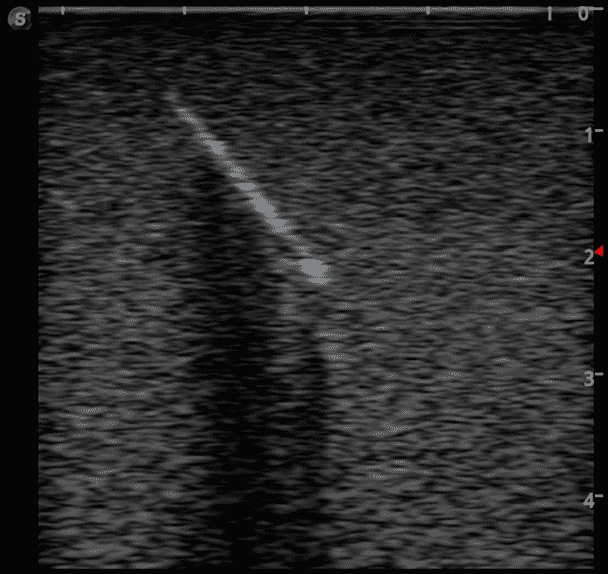

Foreign Body Ultrasound Training Model

Model TYE4033

This training block is designed for training users in the techniques associated with ultrasound guided foreign body identification, targeting, and retrieval.

· High-quality ultrasound images

· Different object depths for various training

· Objects found in the human body including:

Glass shards

Wood splinter

Bullet

Plastic fragments

Metal fragments